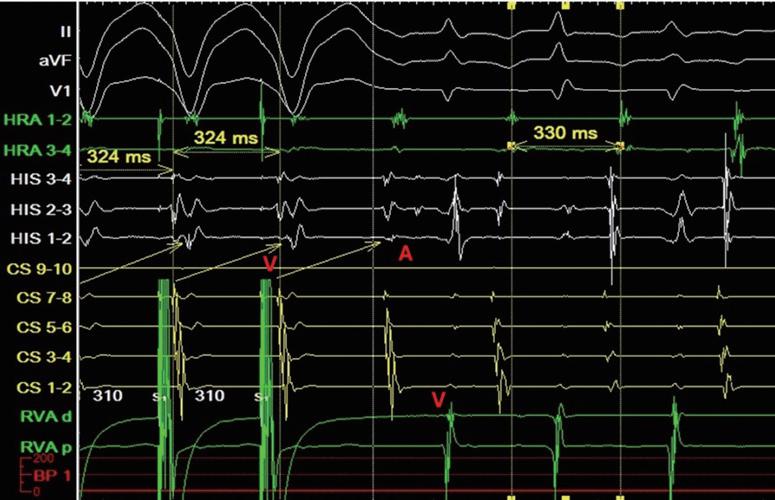

一位 46 歲男性病患去年開始有心悸的症狀。根據 病史詢問,得知患者沒有先天性心臟疾病。因為近日 心悸頻發,所以來到急診求診;發作時的 12 導程心電 圖顯示為short RP tachycardia(HR 220bpm, 如圖一 ),在 急診注射 adenosine 後心律恢復正常, 12 導程心電圖也 沒有異常(圖二)。超音波檢查顯示心臟結構以及左心室 射出分率均正常。經解釋後病患希望接受心臟電生理 檢查併電燒手術。術中放置 CS 導管時, tachycardia 就很容易被導管誘發,根據CS sequence可知為eccentric tachycardia 。放置好診斷管後,電生理檢查發現 RV

S1S1 pacing 時 fast 1 to 1 為 350ms, slow 為 320ms , retrograde fast ERP為280ms,HRA pacing時fast 1 to 1 為

330ms, HRA S1S2 pacing 時 fast ERP 250ms, slow ERP<220ms。Tachycardia很容易被pacing誘發。誘發時 AH 123ms , HA 225ms , AH/HA<1( 圖三 ) , VOP 顯示 為 pseudo VAAV response( 圖四 ) , SA-VA 為 87ms ,

PPI-TCL 為 198ms , His-refractory VPC 顯示 no atrial reset , delta AH 為 37ms 。由以上特徵診斷為 fast-slow AVNRT。在使用RF 50W 50℃ 373 seconds後,fast-slow AVNRT 便無法誘發,術後也未曾復發。根據文獻約有 3% 的 AVNRT 患者同時有 typical AVNRT 和 atypical AVNRT[1],雖然臨床ECG疑似為short RP tachycardia, 但根據電生理檢查,最後仍有可能診斷為 fast-slow AVNRT。

(圖三)、tachycardia時的EGM。

(圖四)、pseudo VAAV response。